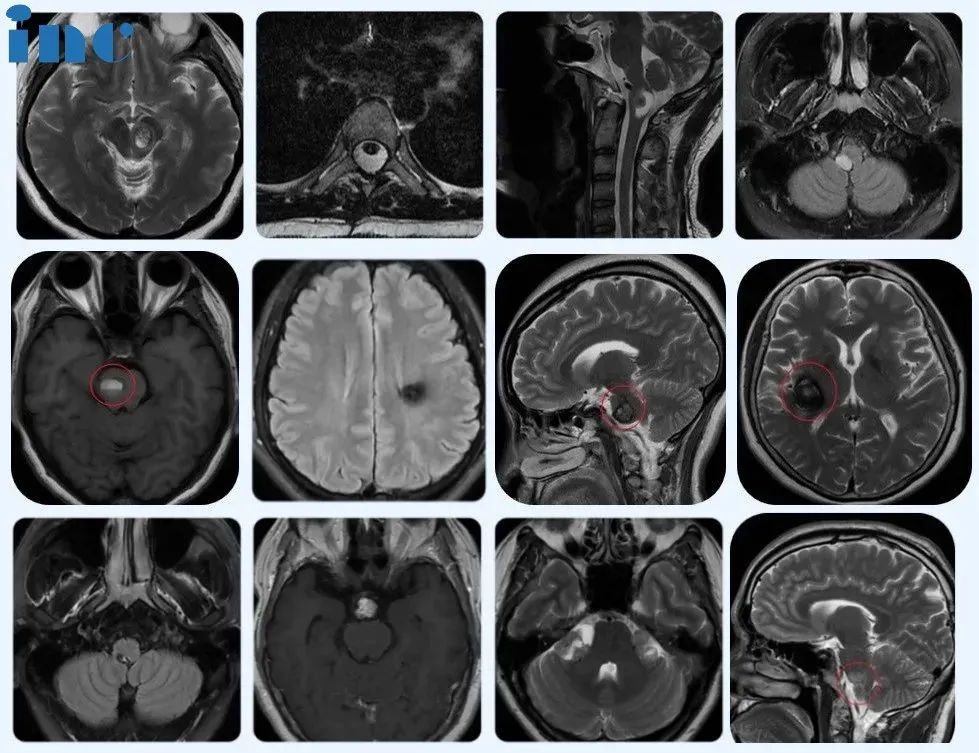

2023年至今,在苏州大学附属儿童医院,除了正常的教学、病例讨论和查房外,巴教授还指导了8例疑难脑瘤患儿的手术。其中脑干部位手术5例,还有小脑、脑室等位置疑难手术,均取得了较为理想的手术效果。

今年,截至目前巴教授指导手术的8个病例的术前磁共振资料,肿瘤位于脑干、脑室、桥臂、颞叶、小脑等疑难位置。

▼部分苏州独墅湖医院巴教授成人手术患者术前影像,接受手术的多名患者肿瘤分别位于脑干、脊髓及丘脑、基底节、桥臂、松果体、鞍区、功能区、CPA桥小脑脚区等疑难位置。